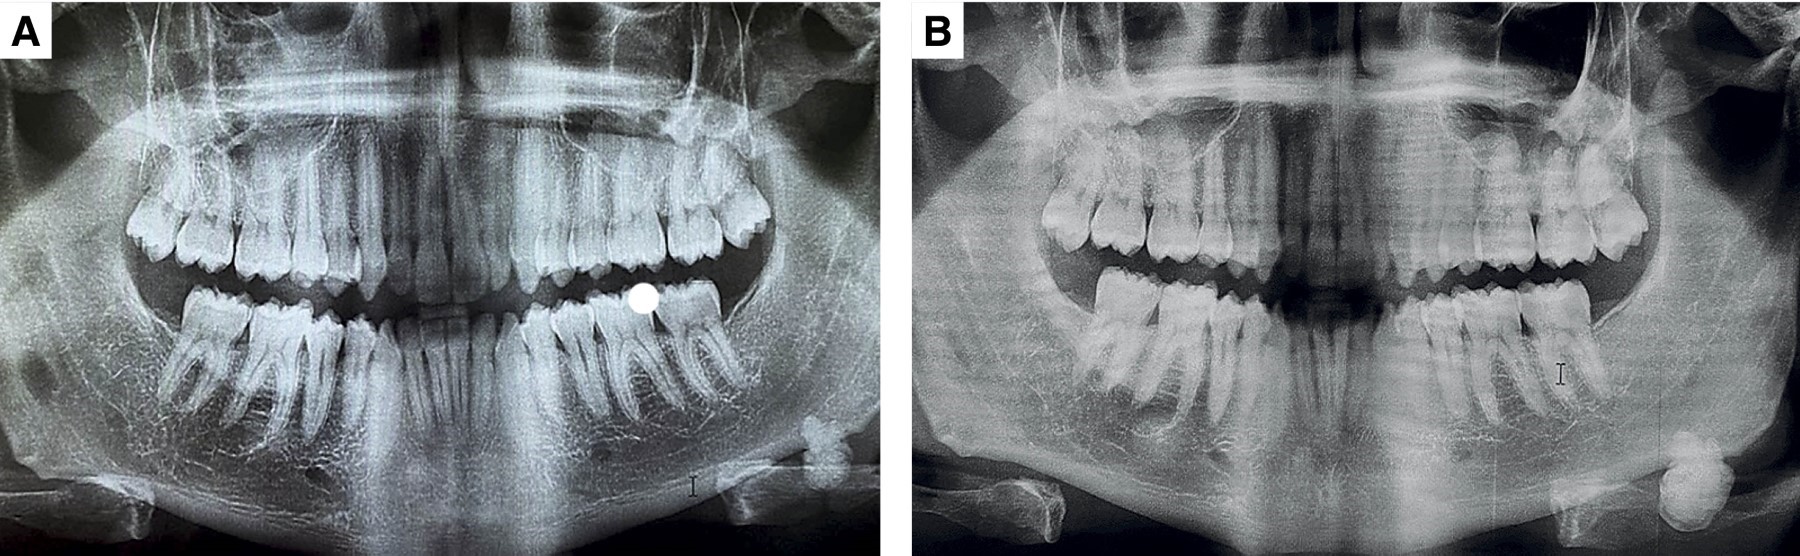

Acude a consulta odontológica donde se solicita la toma de una ortopantomografía de control en la que se identificó una zona radiopaca homogénea de aproximadamente un centímetro de diámetro localizada en la cortical basal de la mandíbula del lado izquierdo, próxima al ángulo mandibular; de aspecto lobulado con bordes bien definidos, asintomática, que pasa desapercibida extraoralmente, de tiempo de evolución desconocido (Figura 1A). Después de tres años refirió crecimiento de la lesión previamente descrita y se realizó nuevamente la toma de estudios de imagen donde se confirmó el aumento de tamaño (Figura 1B). Ante los cambios presentados se decidió realizar la exéresis de la misma bajo el diagnóstico presuntivo de odontoma complejo (Figura 2A). El abordaje se llevó a cabo bajo anestesia general balanceada; previo marcaje quirúrgico para delimitar referencias anatómicas de importancia, infiltración de lidocaína con epinefrina 72 mg/36 μg realizando abordaje tipo Risdon, posterior disección a cuerpo y ángulo mandibular izquierdo. Se procede a la exéresis del tejido (Figura 2B), se verifica hemostasia y cierre del abordaje. Concluye procedimiento sin incidencias ni complicaciones. El espécimen consistió en un fragmento único de tejido duro de 2.5 × 2.3 × 2.2 cm, de forma oval, superficie lobulada, color café claro y consistencia dura (Figura 3).

A la valoración postquirúrgica, después de seis meses del procedimiento, el paciente se encuentra asintomático. En la ortopantomografía de control sólo se observan cambios postquirúrgicos de la resección (Figura 5).

De acuerdo con su localización, pueden clasificarse en periféricos o centrales, siendo esto determinado a su ubicación en el hueso afectado, aquellos que se originan a nivel de la cortical o superficie ósea son clasificados como osteomas periostiales, periféricos o exofíticos y a nivel intramedular denominados osteomas endosteales o centrales.1 La mayoría de veces es una entidad detectada radiográficamente. En el presente caso, fue detectado en un inicio por radiografía, pero con el tiempo, el aumento de tamaño de la lesión fue percibido por el paciente (Figura 1B). En relación con la localización de esta entidad, en el ángulo mandibular y periférico,8 realizaron una revisión de todos los casos de osteomas que afectan el ángulo mandibular, encontrando 32 casos reportados en la literatura inglesa y de los casos de esta revisión junto al presente caso, al realizar la estadística descriptiva, especialmente de los datos clínicos-demográficos de la población afectada (Figura 6), se muestra una mayor prevalencia en el sexo masculino, desde los ocho a los 68 años con una media de 36 años; en relación a los datos clínicos se presenta con mayor frecuencia en la zona del ángulo mandibular del lado izquierdo, con aumento de volumen o asimetría del lado afectado y asintomático; si presenta sintomatología clínica, se ha descrito dolor, disfagia y dificultad al tragar. Con lo anterior, se demuestra que el presente caso descrito posee todas las características clínico-demográficos prevalentes en esta entidad, inclusive, en el presente caso, el osteoma se presenta en el ángulo mandibular, el cual su osificación en esta parte mandibular es de tipo intramembranosa.7-9

Figura 1

Figura 5